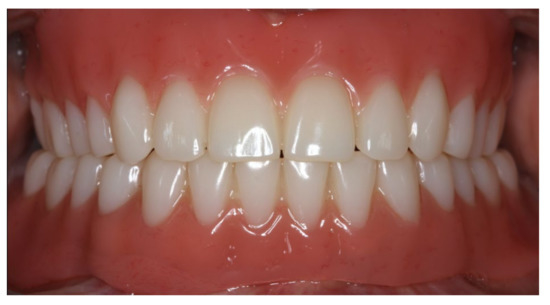

Inserted complete denture in the upper jaw.

Figure 21.

Anterior view of the inserted dentures in centric occlusion.

During the final appointment, the Locator abutments were tightened with torque (0.35 Nm) and the dentures were inserted. The attachment patrices were equipped with inserts producing intermediate retention (green). Occlusion, extension, retention, and aesthetics were carefully controlled and adjusted where appropriate (Figure 19, Figure 20 and Figure 21). Both dentures featured excellent retention and fit. Finally, the patient was instructed regarding insertion, removal, and maintenance of the dentures. After one week, the patient was satisfied with the new prostheses and no complications were reported or identified.